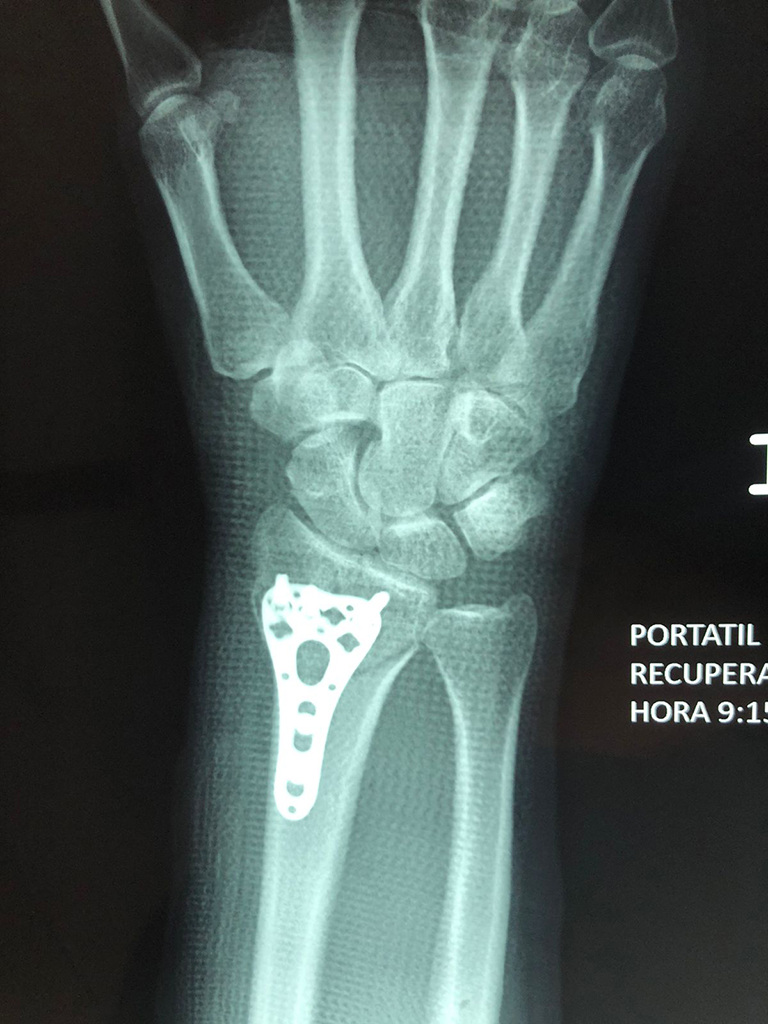

Calcaneo - Cirugías de Muñecas y Manos

Los procedimientos más comunes en cirugía de la mano son aquellos destinados a reparar traumatismos, incluyendo lesiones de tendones, nervios, vasos sanguíneos, y articulaciones; huesos fracturados; y quemaduras, cortes, y otros daños de la piel.